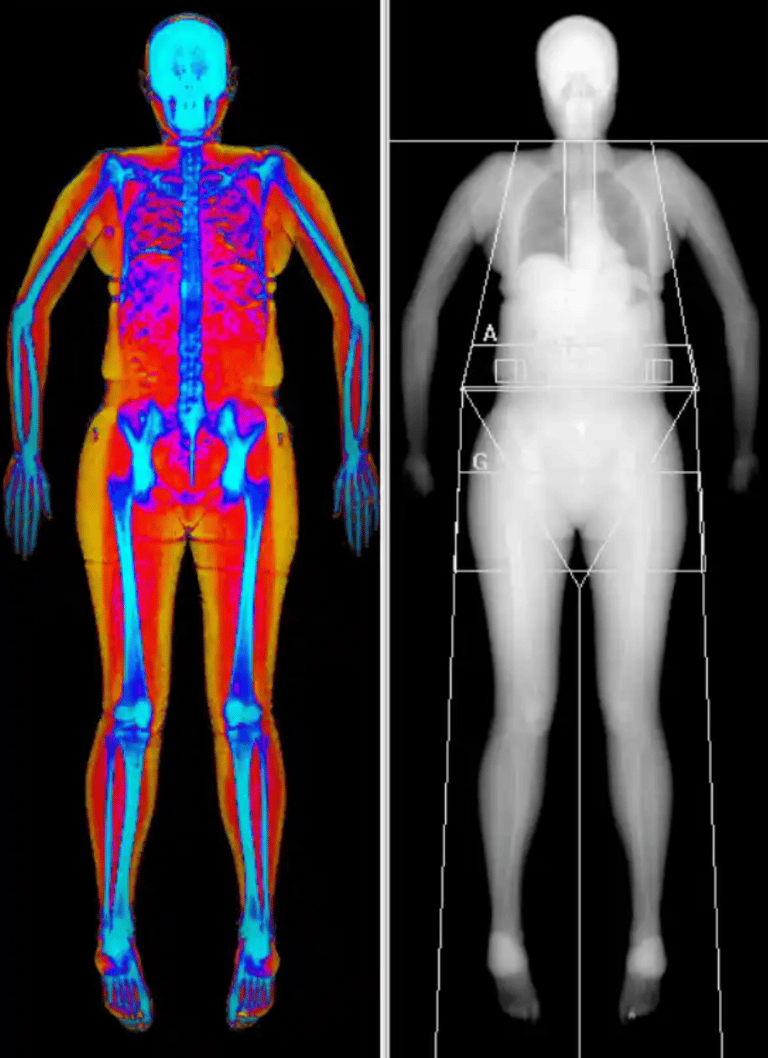

DEXA body composition – analysis of fat, muscle mass and fat distribution

DEXA is one of the most precise methods for mapping body composition and provides detailed measurements of fat mass, muscle mass and how fat is distributed in the body. The examination shows not only how much body fat you have, but also where it is located, including the difference between subcutaneous fat and visceral fat around the internal organs.

The results are presented both visually and in numbers, making it possible to follow changes over time and identify patterns that are not visible on the scale.